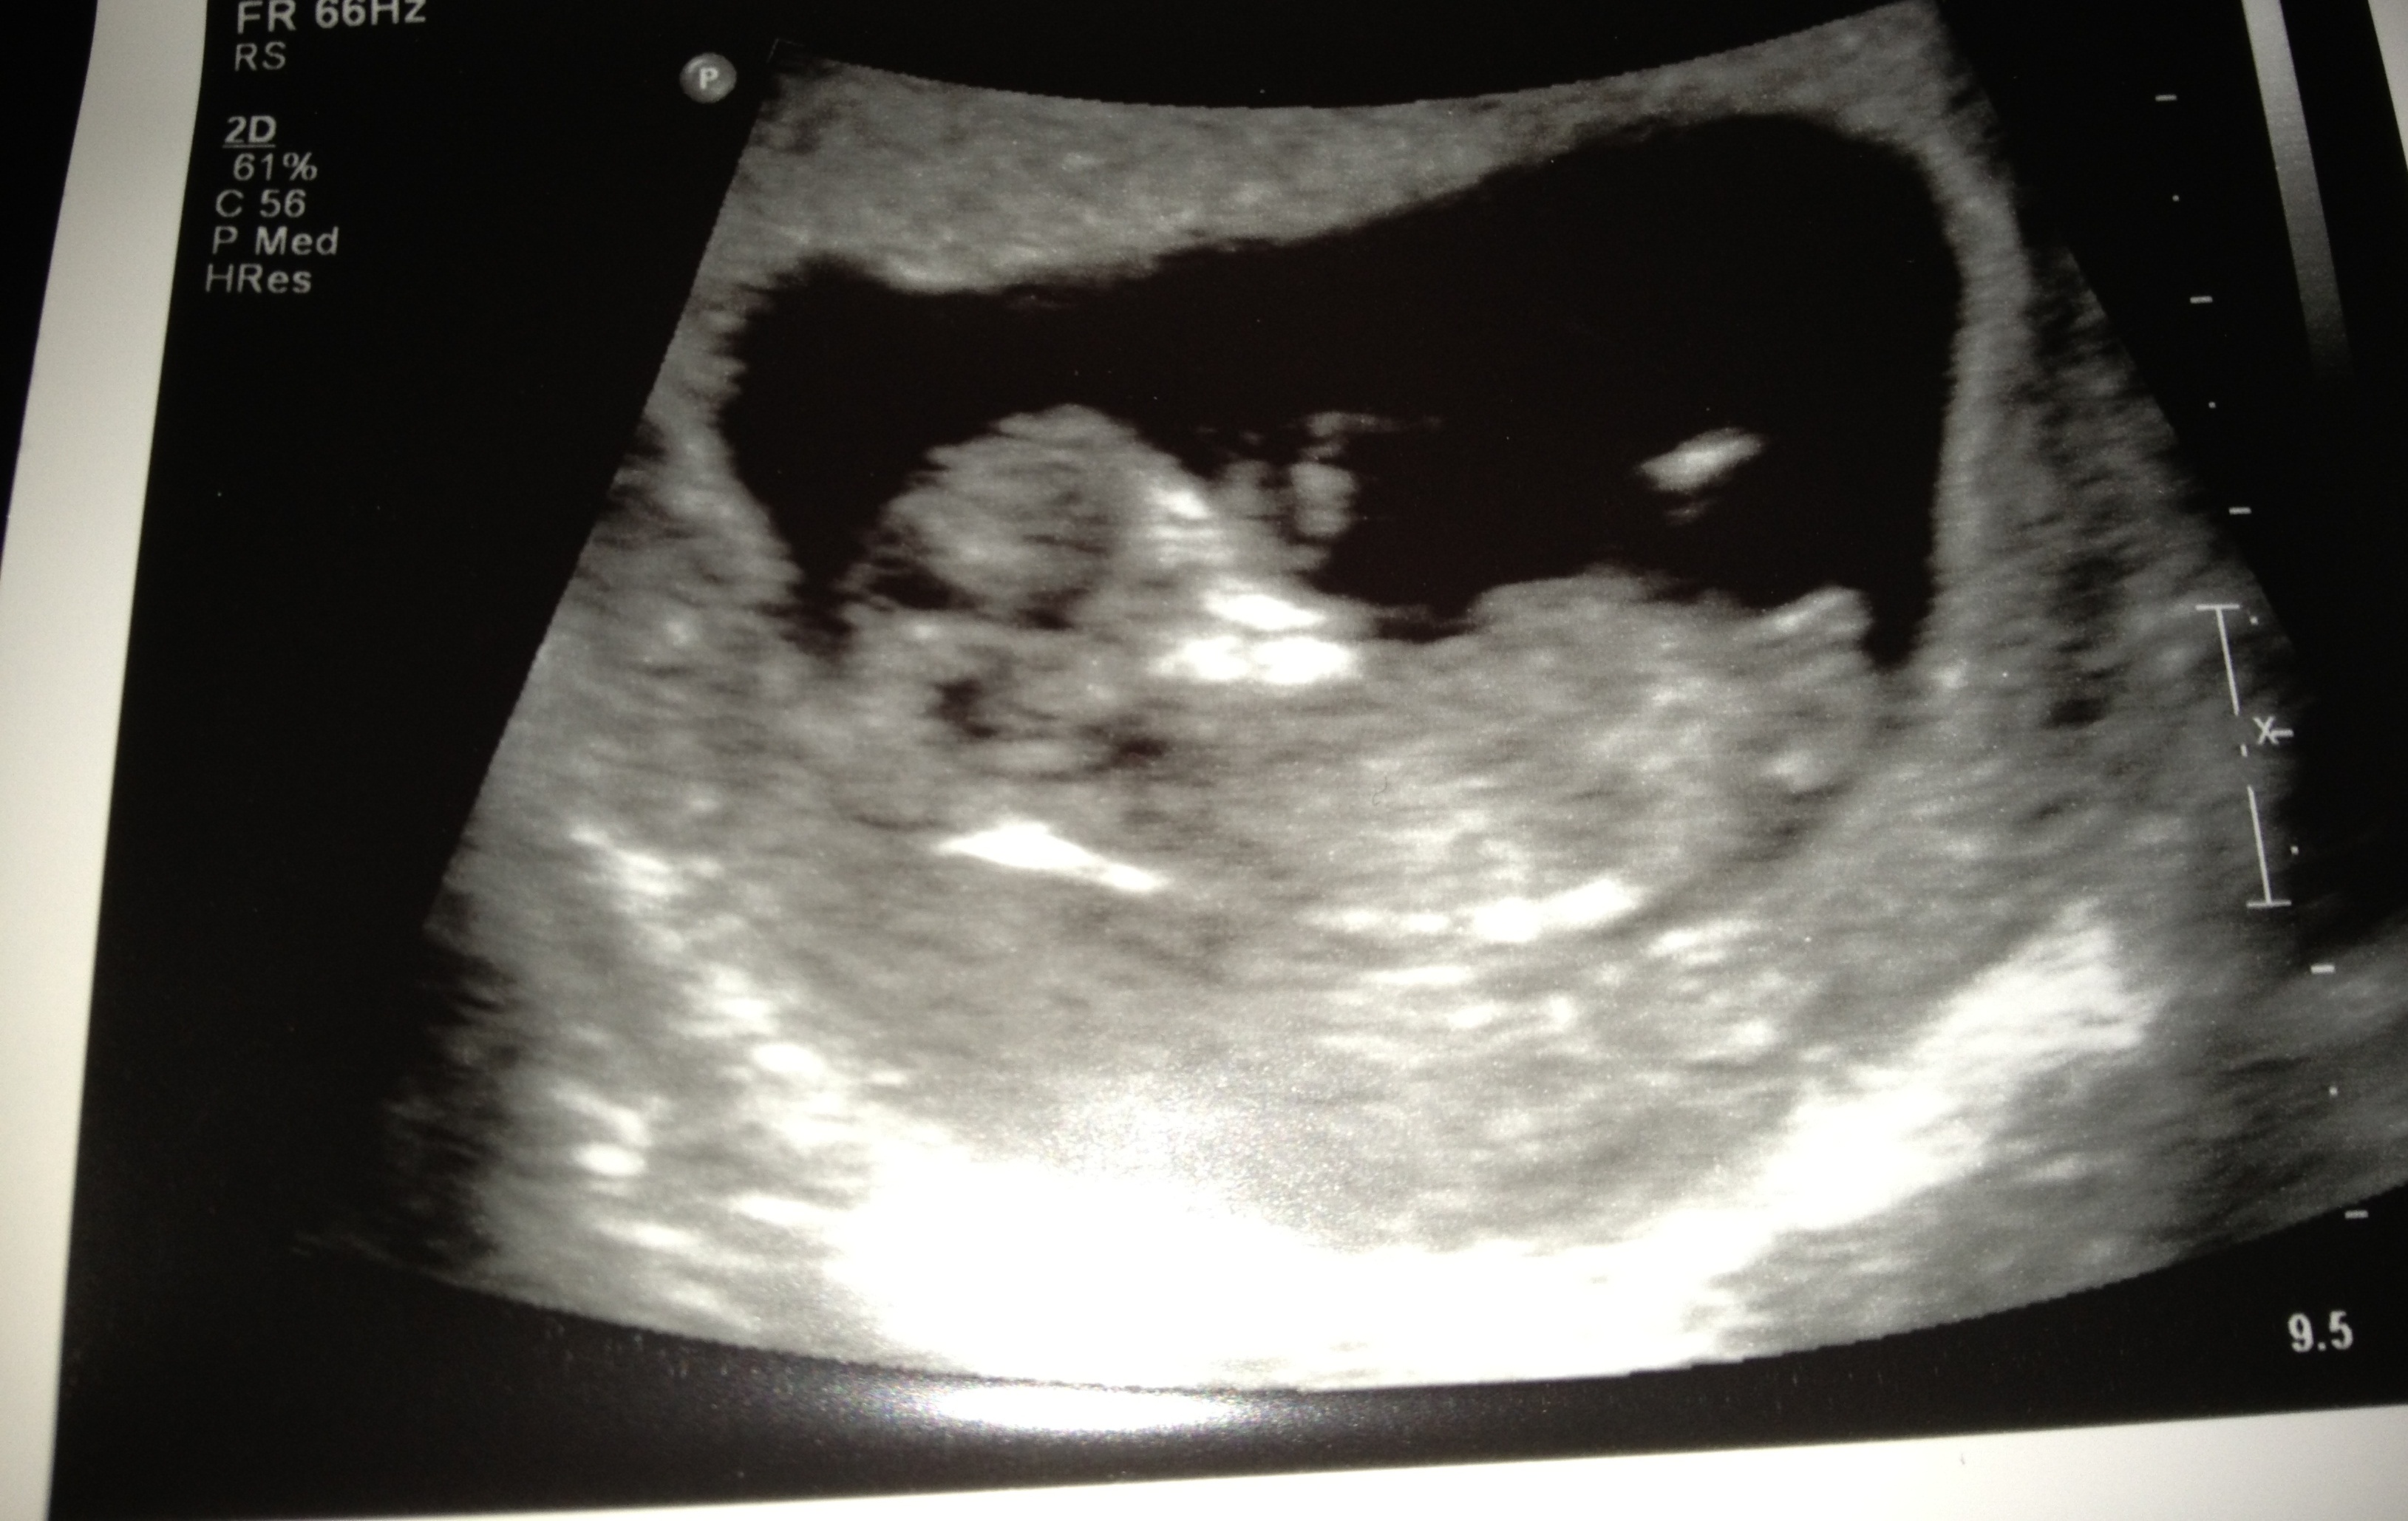

Im guessing a boy....

Looks early but the nub is flat at the moment so guessing pink.

Girl guess from me:)

How far gone is your pregnancy in this scan? Thinking possibly girl...

Thanks for the response. 11 weeks 4 days. I was hoping for a scan next week but had to have an emergency U/S a week early.